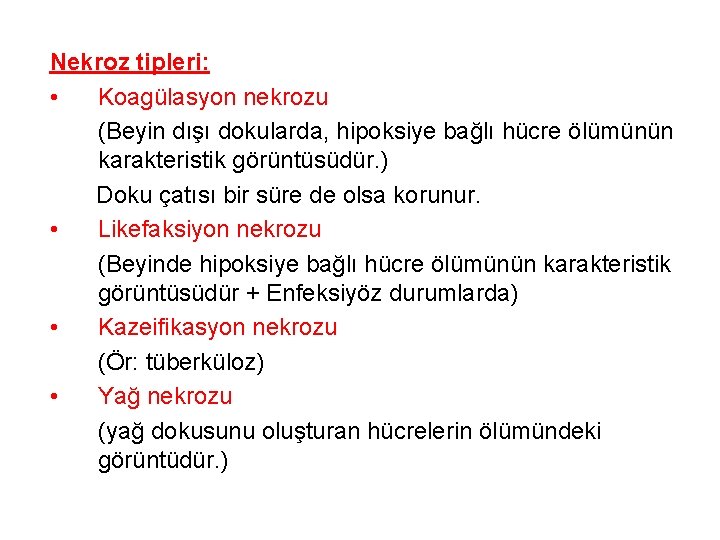

Nekroz tipleri: • Koagülasyon nekrozu (Beyin dışı dokularda, hipoksiye bağlı hücre ölümünün karakteristik görüntüsüdür. ) Doku çatısı bir süre de olsa korunur. • Likefaksiyon nekrozu (Beyinde hipoksiye bağlı hücre ölümünün karakteristik görüntüsüdür + Enfeksiyöz durumlarda) • Kazeifikasyon nekrozu (Ör: tüberküloz) • Yağ nekrozu (yağ dokusunu oluşturan hücrelerin ölümündeki görüntüdür. )